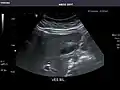

Aorta: Visualized portions normal in caliber, 16 x 15 mm.

Aorta -